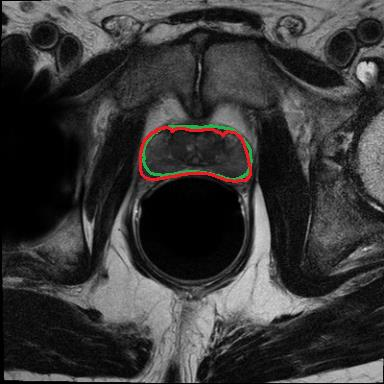

Modern deep neural networks struggle to transfer knowledge and generalize across diverse domains when deployed to real-world applications. Currently, domain generalization (DG) is introduced to learn a universal representation from multiple domains to improve the network generalization ability on unseen domains. However, previous DG methods only focus on the data-level consistency scheme without considering the synergistic regularization among different consistency schemes. In this paper, we present a novel Hierarchical Consistency framework for Domain Generalization (HCDG) by integrating Extrinsic Consistency and Intrinsic Consistency synergistically. Particularly, for the Extrinsic Consistency, we leverage the knowledge across multiple source domains to enforce data-level consistency. To better enhance such consistency, we design a novel Amplitude Gaussian-mixing strategy into Fourier-based data augmentation called DomainUp. For the Intrinsic Consistency, we perform task-level consistency for the same instance under the dual-task scenario. We evaluate the proposed HCDG framework on two medical image segmentation tasks, i.e., optic cup/disc segmentation on fundus images and prostate MRI segmentation. Extensive experimental results manifest the effectiveness and versatility of our HCDG framework.